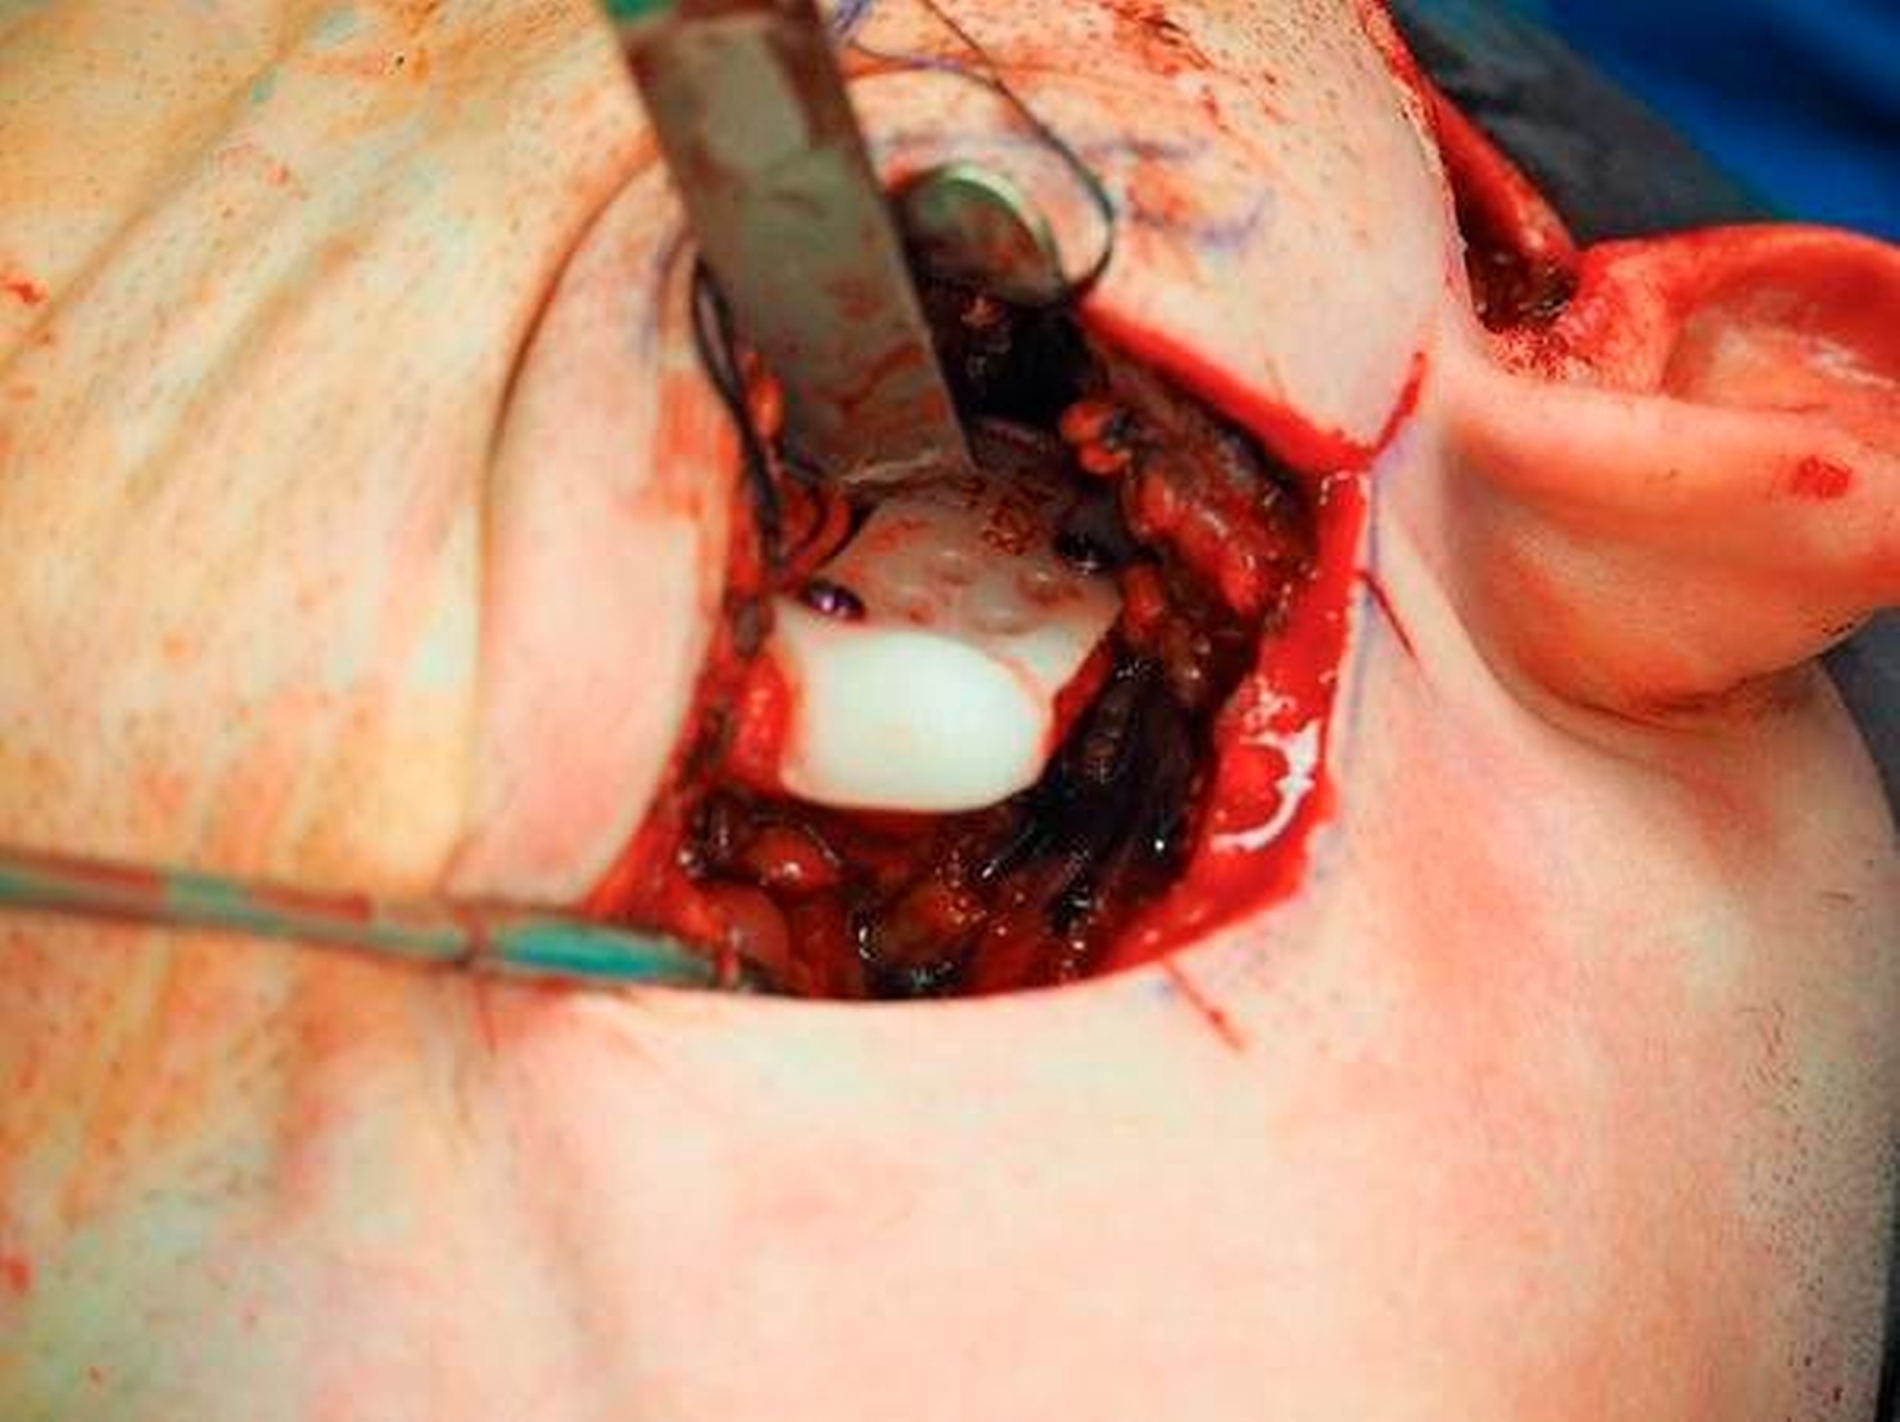

Nach Akzeptanz des Behandlungsplans wurden die TEPs (Totalendoprothesen) beidseits über jeweils einen präaurikulären und einen retromandibulären Zugang implantiert. Diese Prothesen wurden mit Schrauben – mit exakt am CT-Datensatz definierten Schraubenlängen – fixiert. Bei der Planung der Schraubenpositionierung wurde der Verlauf des N. alveolaris inferior berücksichtigt und der Nerv geschont.

Vor der definitiven Fixierung der Prothesen wurden Dummys als Test eingesetzt, um eine optimale Positionierung der passgenauen finalen Prothesen zu erreichen (Abbildung 2 bis 9). Abbildung 10a und 10b zeigen die postoperative Röntgenkontrolle.